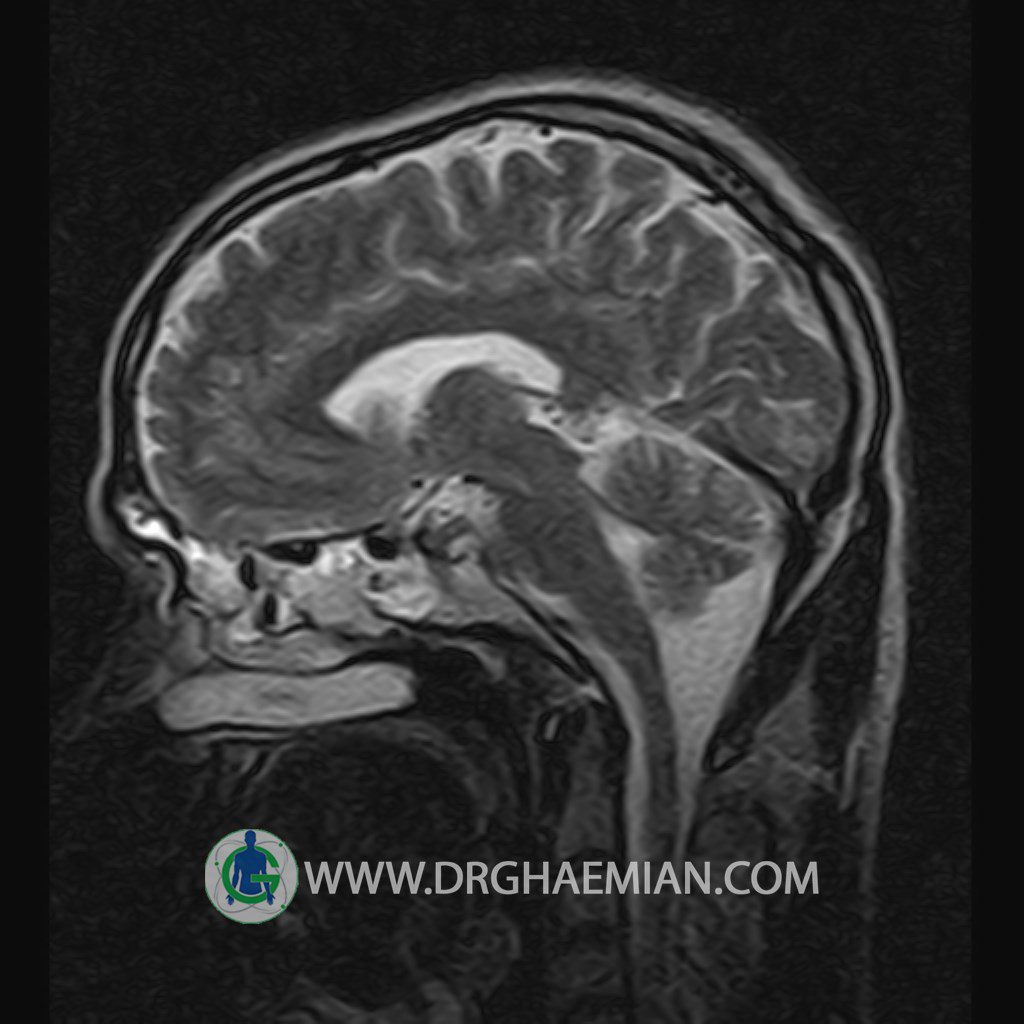

پزشکان اغلب از تصویربرداری ام آر آی برای تشخیص و درمان عارضه های پزشکی که فقط با استفاده از اشعه ایکس یا میدان مغناطیسی و امواج رادیویی قابل مشاهده است، استفاده می کنند. دستگاه ام آر آی تصاویر دقیق از ساختار های داخلی بدن ایجاد می کند. در این کیس یک میکروآدنوم در هیپوفیز بیمار مشاهده می شود.

HYPOPHYSIS MRI

(with and without contrast)

Technique: Axial , coronal T1 , Axial , coronal , sagittal T2 , Axial, coronal T1 post Gd & 64 dynamic thin coronal slices.

REPORT :

– Small hypoenhancing mass lesion ( 3 x 4 mm ) in posterior of pituitary stalk suggestive for micro adenoma